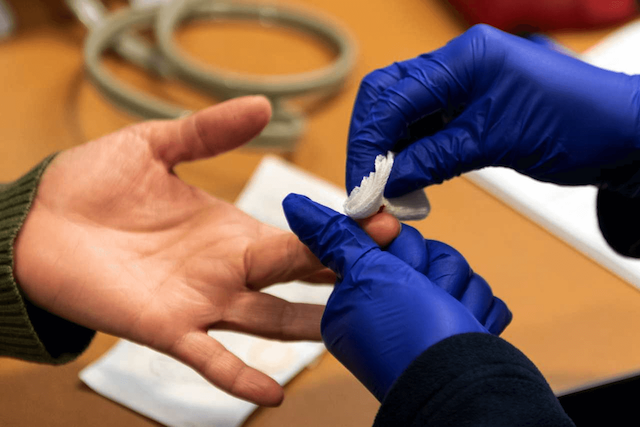

UCLA Health 医疗中心琼森综合癌症中心(UCLA Health Jonsson Comprehensive Cancer Center)的研究人员从美国国家癌症研究所(NCI)获得了总计 910 万美元的资助,用于推进液体活检技术,从而推进癌症早期的检测。液体活检技术的优化将显着改善治疗方式和模式,并有效减少癌症导致的死亡人数。

液体活检(liquid biopsy)是一种前景可观的非侵入性医学测试,使用少量血液,就可以帮助科学家深入了解肿瘤的基因构成。通过分析血液成分,还可以帮助医生获得有关与癌症存在相关的基因突变、改变和其他分子变化的宝贵信息。

首席研究员 Jasmine Zhou 博士以及 David Geffen 医学院和 Jonsson 综合癌症中心的 Steven-Huy Han 博士、Samuel French 博士和 Vatche Agopian 博士将利用来自美国国家癌症研究所的第一笔资金开发、并验证整合血液、成像和临床数据,以检测早期肝癌的液体活检方法。

来自美国国家癌症研究所的第二笔资金,将用于优化无细胞 DNA 甲基化组,对定位结肠癌、胃癌、肝癌和肺癌的早期检测。

- 血液检查:一组检查肝功能的实验室检查。